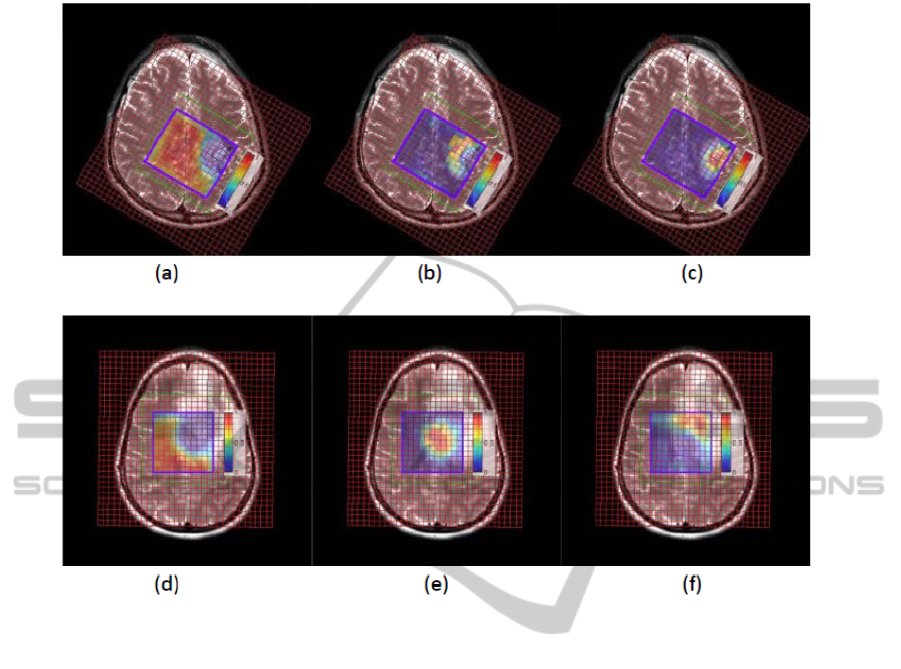

TISSUE TYPE DIFFERENTIATION FOR BRAIN GLIOMA USING NON-NEGATIVE MATRIX FACTORIZATION